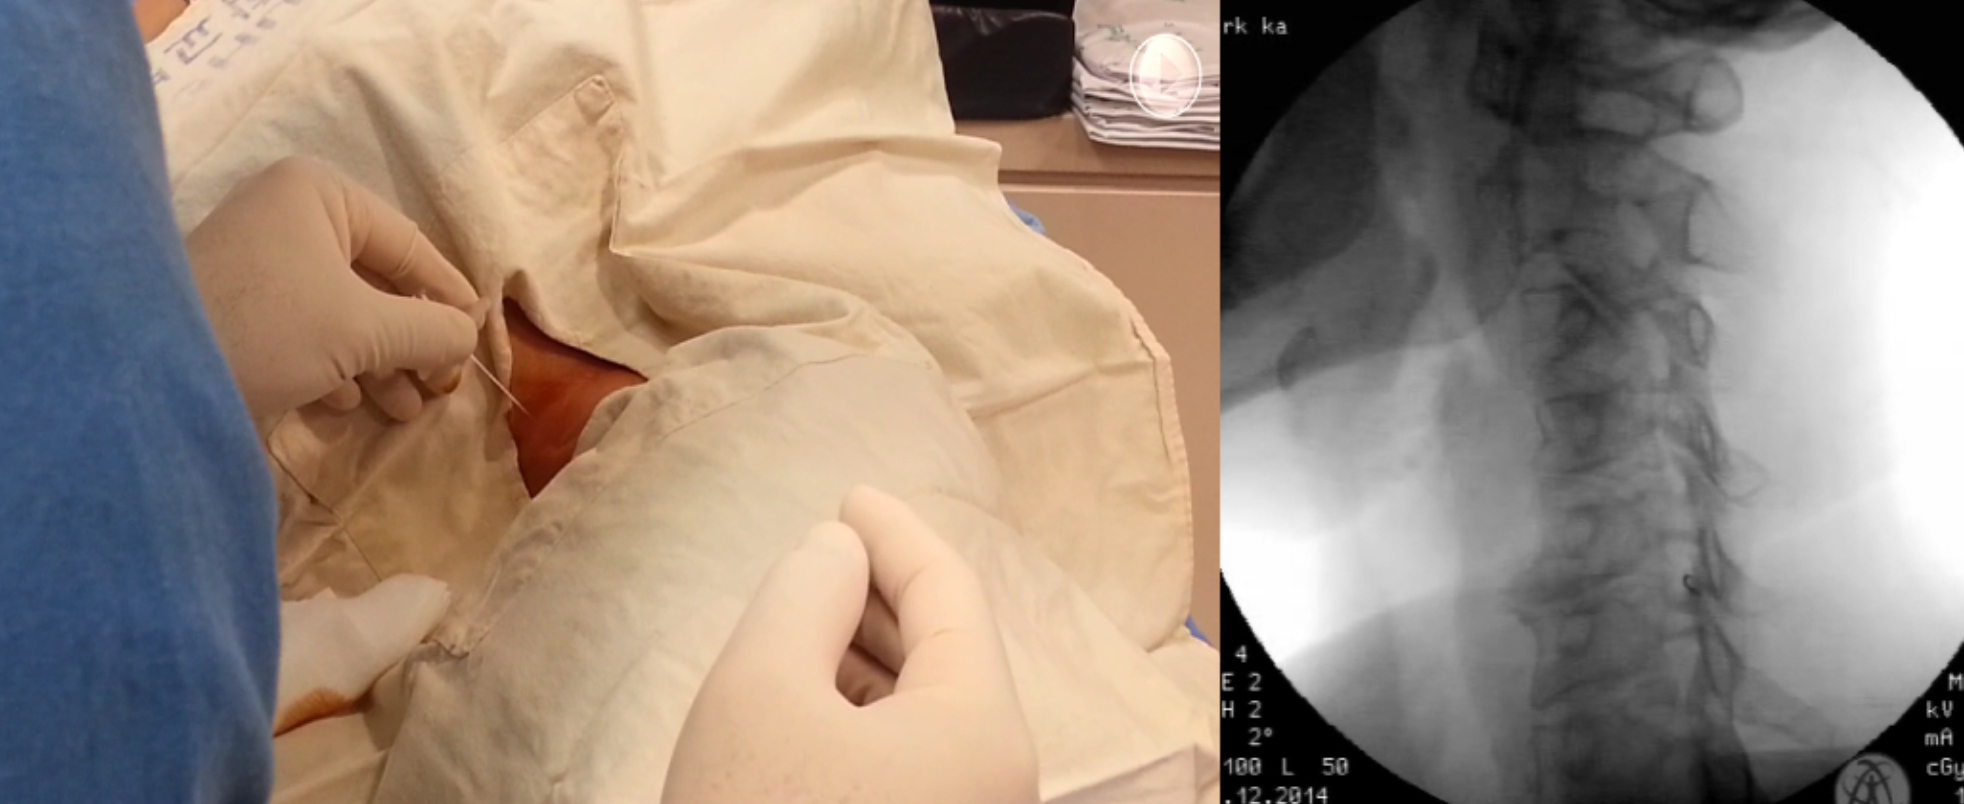

Fluoroscopy guide injection

TFESI

Procedure